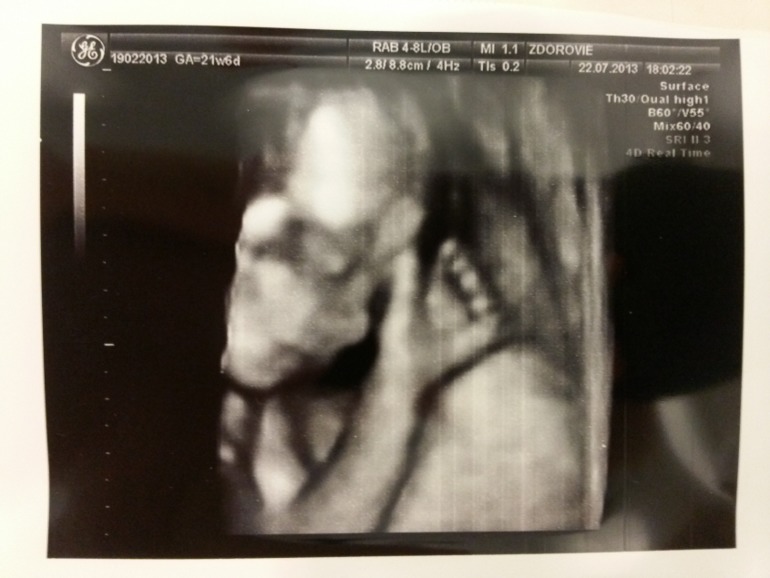

А вот и на фото наша малышка, лежала спокойно) пока ее рассматривали, на одной фотографии даже язык нам показала )))

Вот-вот, она язычок показывает )